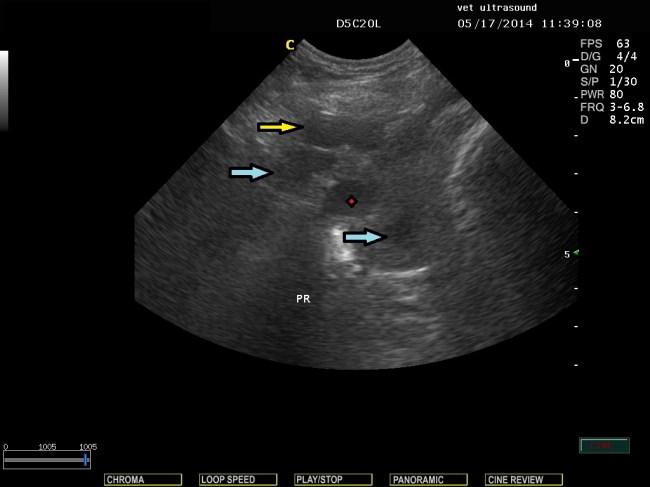

Το κίτρινο βέλος δείχνει μία παραπροστατική κύστη η οποία καλύπτεται μόνο από την κάψα του αδένα.

Τα μπλέ βέλη δείχνουν δύο ενδοπροστατικές κύστεις

Το κόκκινο αστέρι δείχνει την διατεταμένη ουρήθρα.